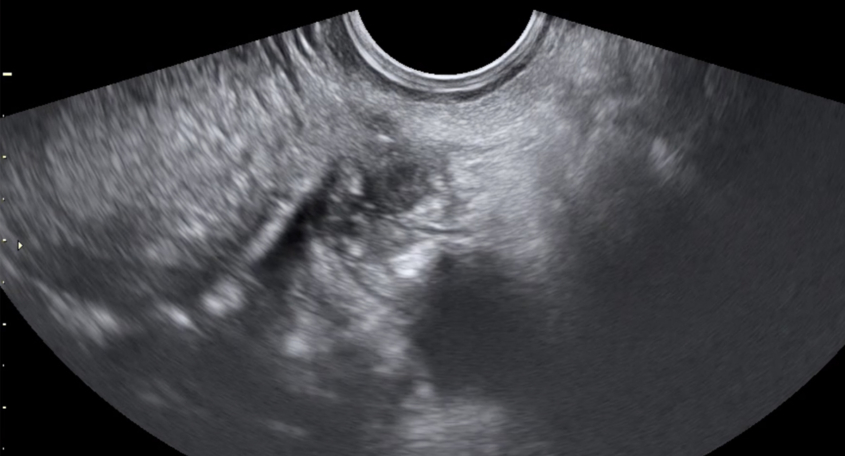

Transvaginal ultrasound.

Transvaginal ultrasonography is the imaging technique of choice for endometriosis; it is easily accessible, non-invasive and approachable, providing the specialist with a plethora of information. It also allows the clinician to perform a bimanual palpation (to press on the abdomen and see how certain organs mobilise in relation to other organs and the transducer). Ultrasound provides a lot of information if the examiner knows the pathology and knows how to integrate it into the clinical picture.